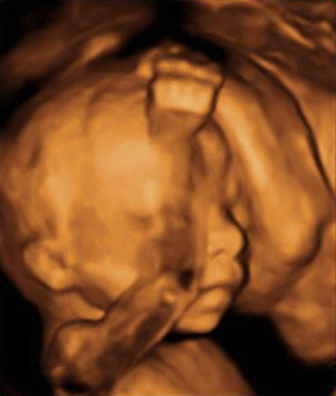

En la ecografía en 3D vemos a un bebé de 20 semanas de gestación se tapa la cara con ambos brazos y aprieta los puños. Se trata de un gesto innato que mantendrá en la cuna durante los primeros meses de vida.

Imagen de bebé tapándose la cara con ambos brazos

Ecografía Embarazo 2D y 3D - SEMANA 20